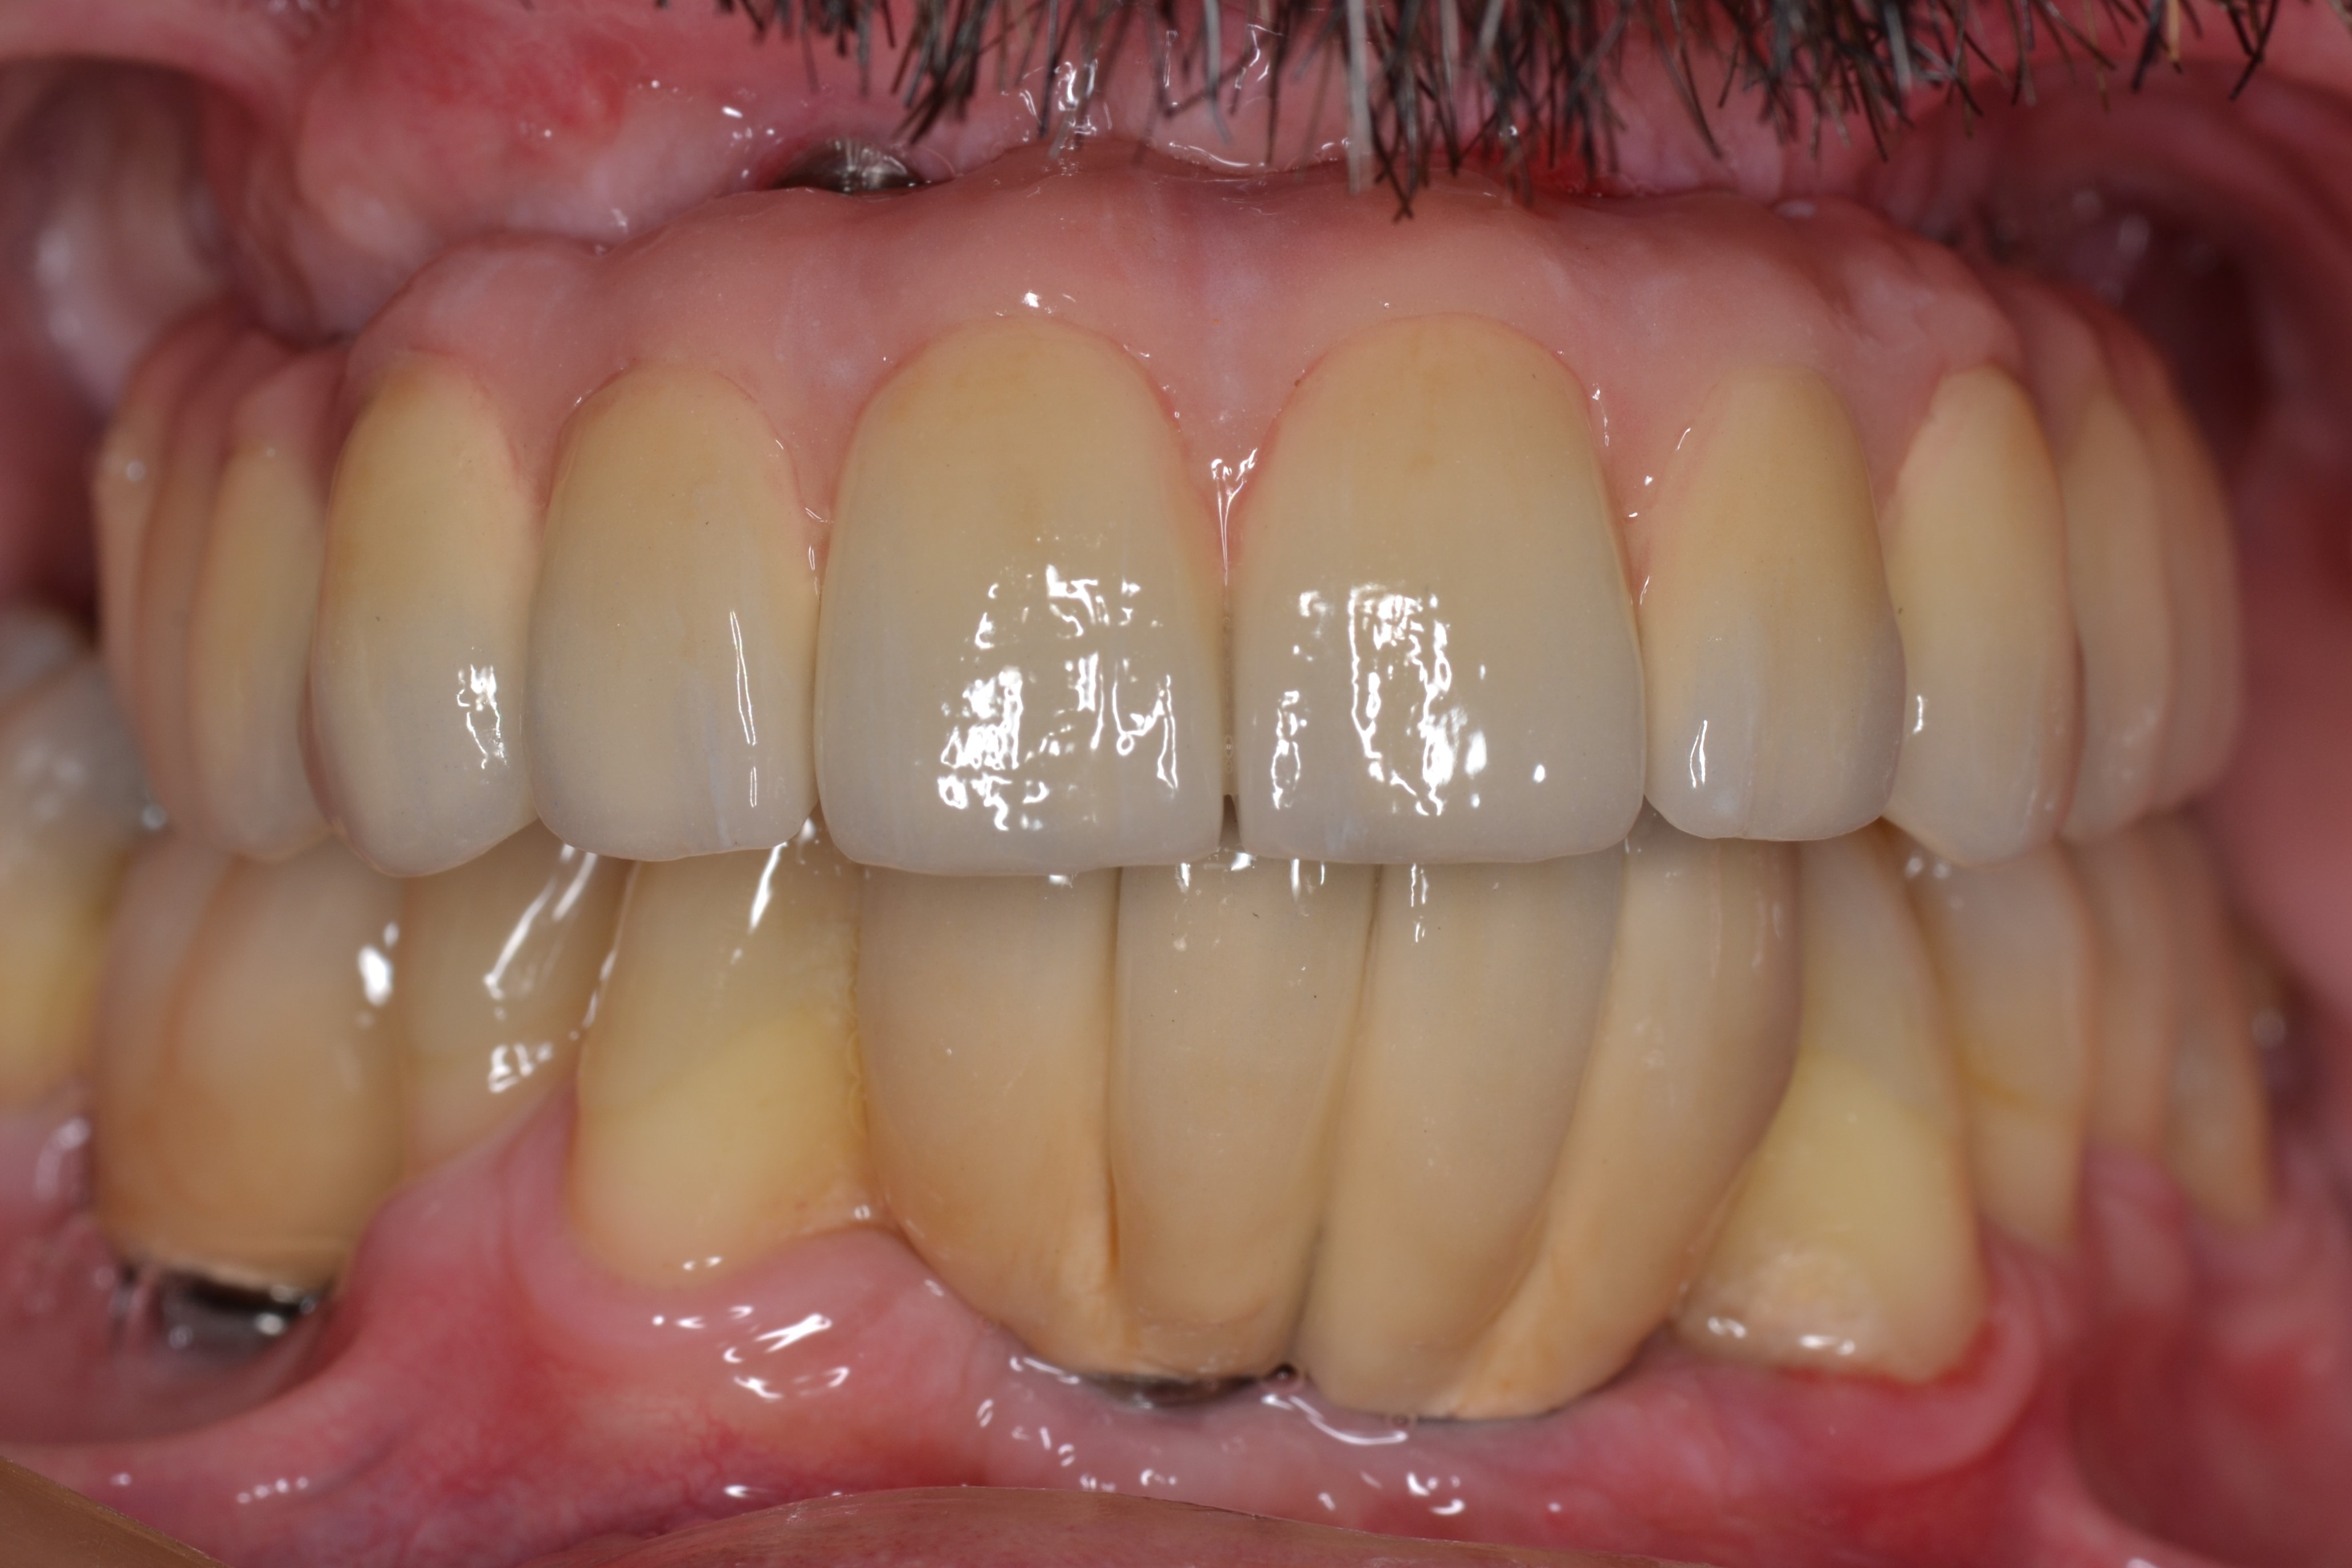

Ο ασθενής αυτός ήταν έντονα δυσαρεστημένος με την εμφάνιση των άνω και κάτω δοντιών του. Τα δοντια του ηταν σε τερματικό στάδιο και η μάσηση ήταν σχεδόν αδύνατη.

Με την χρήση οδοντικών εμφυτευμάτων καταφέραμε να αποκαταστήσουμε το στόμα του.

Οι νέες μεταλλοκεραμικές γέφυρες που κατασκευάστηκαν, αποκατέστησαν την αισθητική ισορροπία του χαμόγελου, την σωστή μάσηση και επανέφεραν την αυτοπεποίθηση του ασθενούς.